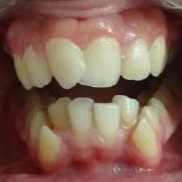

مکیدن انگشت شست و پستانک چه تاثیر مخربی بر روی دندان های کودک دارد؟

چگونه میتوانم دندان کج خود را صاف کنم؟